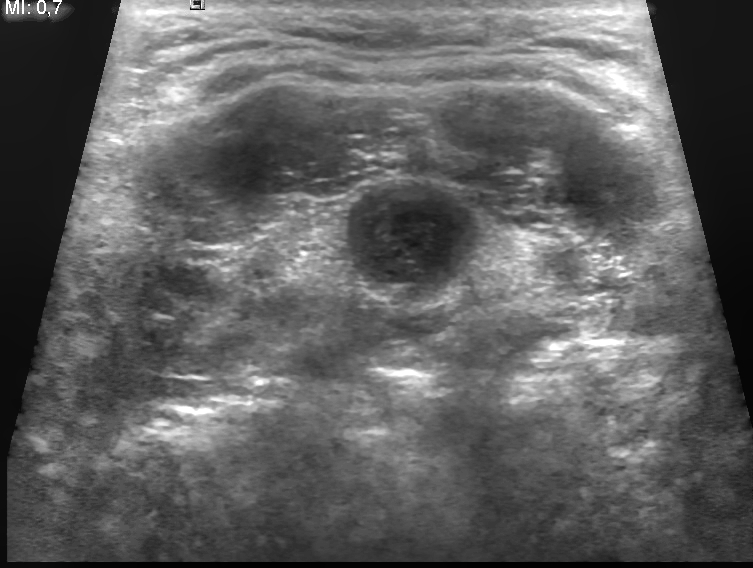

Thyroid nodules are more likely to be benign than malignant, and thyroid neoplasia usually appears as a distinct, solitary nodule.

I-131 radioactive uptake studies are useful to further characterize nodules.

Increased uptake (hot nodule) is seen in Graves’ disease or nodular goiter.

Decreased uptake (cold nodule) is seen in adenoma and carcinoma and they often warrant biopsy.

Biopsy is performed by fine needle aspiration (FNA).